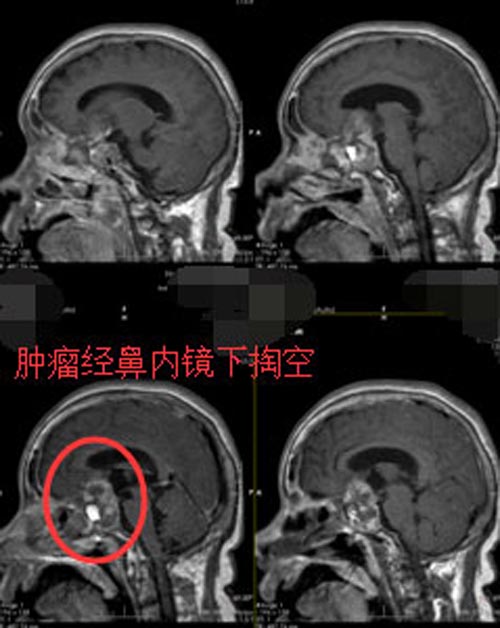

由鲁明副院长主刀实施“经鼻蝶鞍区垂体大腺瘤切除术”,手术过程顺利。由于手术是经鼻微创,不需要开颅,所以蔡阿姨术后恢复得比较快。

▲手术后